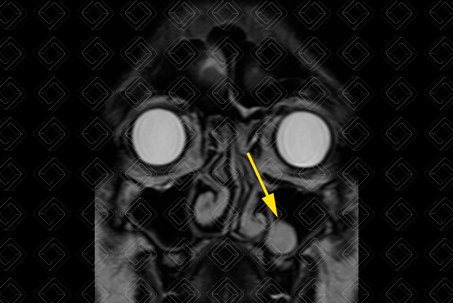

Texto alternativo para a imagem Figura 1. Créditos: Dra. Elazir Mota - Rio de Janeiro/RJ

Descrição da figura 1: Tomografia computadorizada da face com reconstrução coronal, em que se observa imagem lobulada, com densidade cística, no assoalho do seio maxilar direito (seta vermelha).

• Tomografia computadorizada dos seios da face (figura 1): Imagem ovalada ou arredondada, de contornos lobulados, com densidade cística na tomografia (densidade variando de 0-20UH);